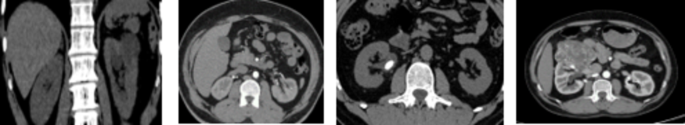

The dataset, which was collected from the CT KIDNEY DATASET (https://www.kaggle.com/datasets/nazmul0087/ct-kidney-dataset-normal-cyst-tumor-and-stone) collection and available to the public, consists of CT images acquired from persons diagnosed with kidney diseases in multiple hospitals throughout Bangladesh22. In this study 8570 distinct CT scan images taken from the dataset, including kidney cysts, stones, tumours, and normal kidneys. Coronal and axial slices were selected based on the methodology for measuring the whole abdomen and urogram, from both contrast and non-contrast testing. There are precisely 2500 images displaying kidney cysts, 1370 images showing kidneys affected by stones, and 2200 images displaying kidneys affected by tumours. The data collection consists of images with a pixel resolution of 705 × 569, with both the horizontal and vertical dimensions set at 96 × 96 dots per inch (dpi) is shown in Fig. 7.